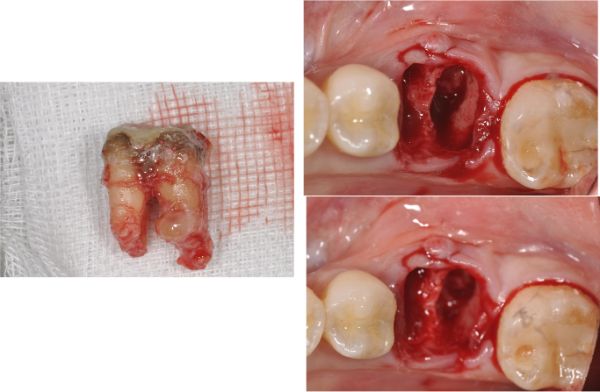

治療前,左下第一大臼齒根尖病變

根尖病變

手術後牙齦仍腫脹

拔牙後待傷口癒合